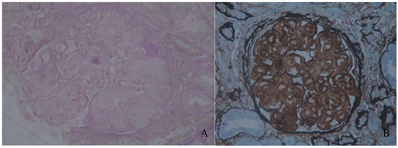

肾脏病理:光镜,患者于2018年8月27日进行肾穿刺。肾活检光镜下检查(图1)显示:3条皮髓交界肾组织,共25个肾小球。肾小球呈分叶状,肾小球系膜区中至重度增宽,系膜区可见均质样物质沉积,基底膜增厚。毛细血管袢开放欠佳,囊壁无增厚。系膜区可见少量嗜复红物沉积。肾小管上皮细胞颗粒变性,蛋白管型形成,肾小管小灶状萎缩(20%),基底膜增厚。肾间质小灶状淋巴细胞及单核细胞浸润,伴纤维化(20%)。小动脉未见明显异常。刚果红染色阴性。免疫荧光:8个肾小球,IgA、IgM、C3、C4、C1q、IgG、FRA、κ、λ、HBsAg、HBcAg均为阴性。